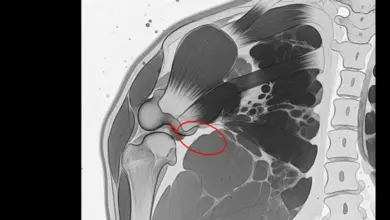

- Ressonância magnética: exame mais completo para ruptura completa do manguito rotador, pois define o tamanho, retração, tendões envolvidos e sinais de degeneração muscular, dados importantes para planejar o tratamento.

Na ruptura completa do manguito rotador, existe rompimento em toda a espessura do tendão, com descolamento do osso.

Dependendo do tempo de evolução, pode ocorrer retração do tendão e degeneração do músculo, fatores que pesam na decisão terapêutica e no prognóstico.